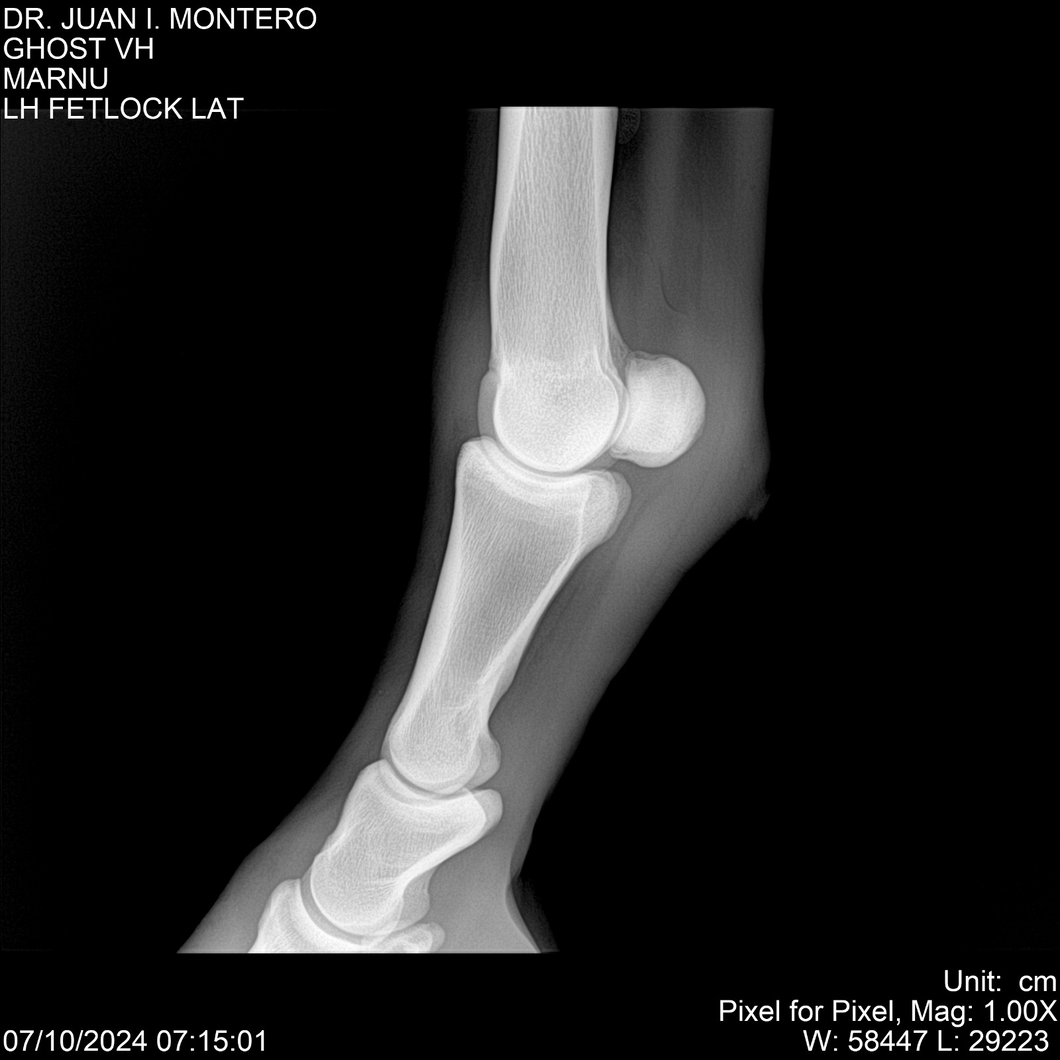

LOTE 15, GHOST VH 🔥 🔥 🔥 Lote Anterior Volver al remate Lote Siguiente Ficha Contacto Montevideo - Ficha del Lote Identificador: #282525 Categoría: Yeguarizos Montevideo - 69 Visualizaciones ClicData Contacto Empresa: Abelenda N. R., Walter Hugo Nombre*: Teléfono* : E-mail* : Mensaje Enviar Registrese gratis Este contenido Exclusivo está disponible sólo para usuarios registrados Ingresar